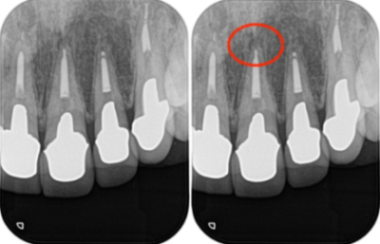

当院にて詳しく診査を行ったところ、左上1番の歯に根尖性歯周炎(虫歯や歯髄炎が進行し、歯の根の先周辺の歯周組織に炎症が生じた状態)が確認されました。

この炎症が、患者様が感じていた違和感の主な原因であると診断しました。

レントゲン画像がこちらになります。